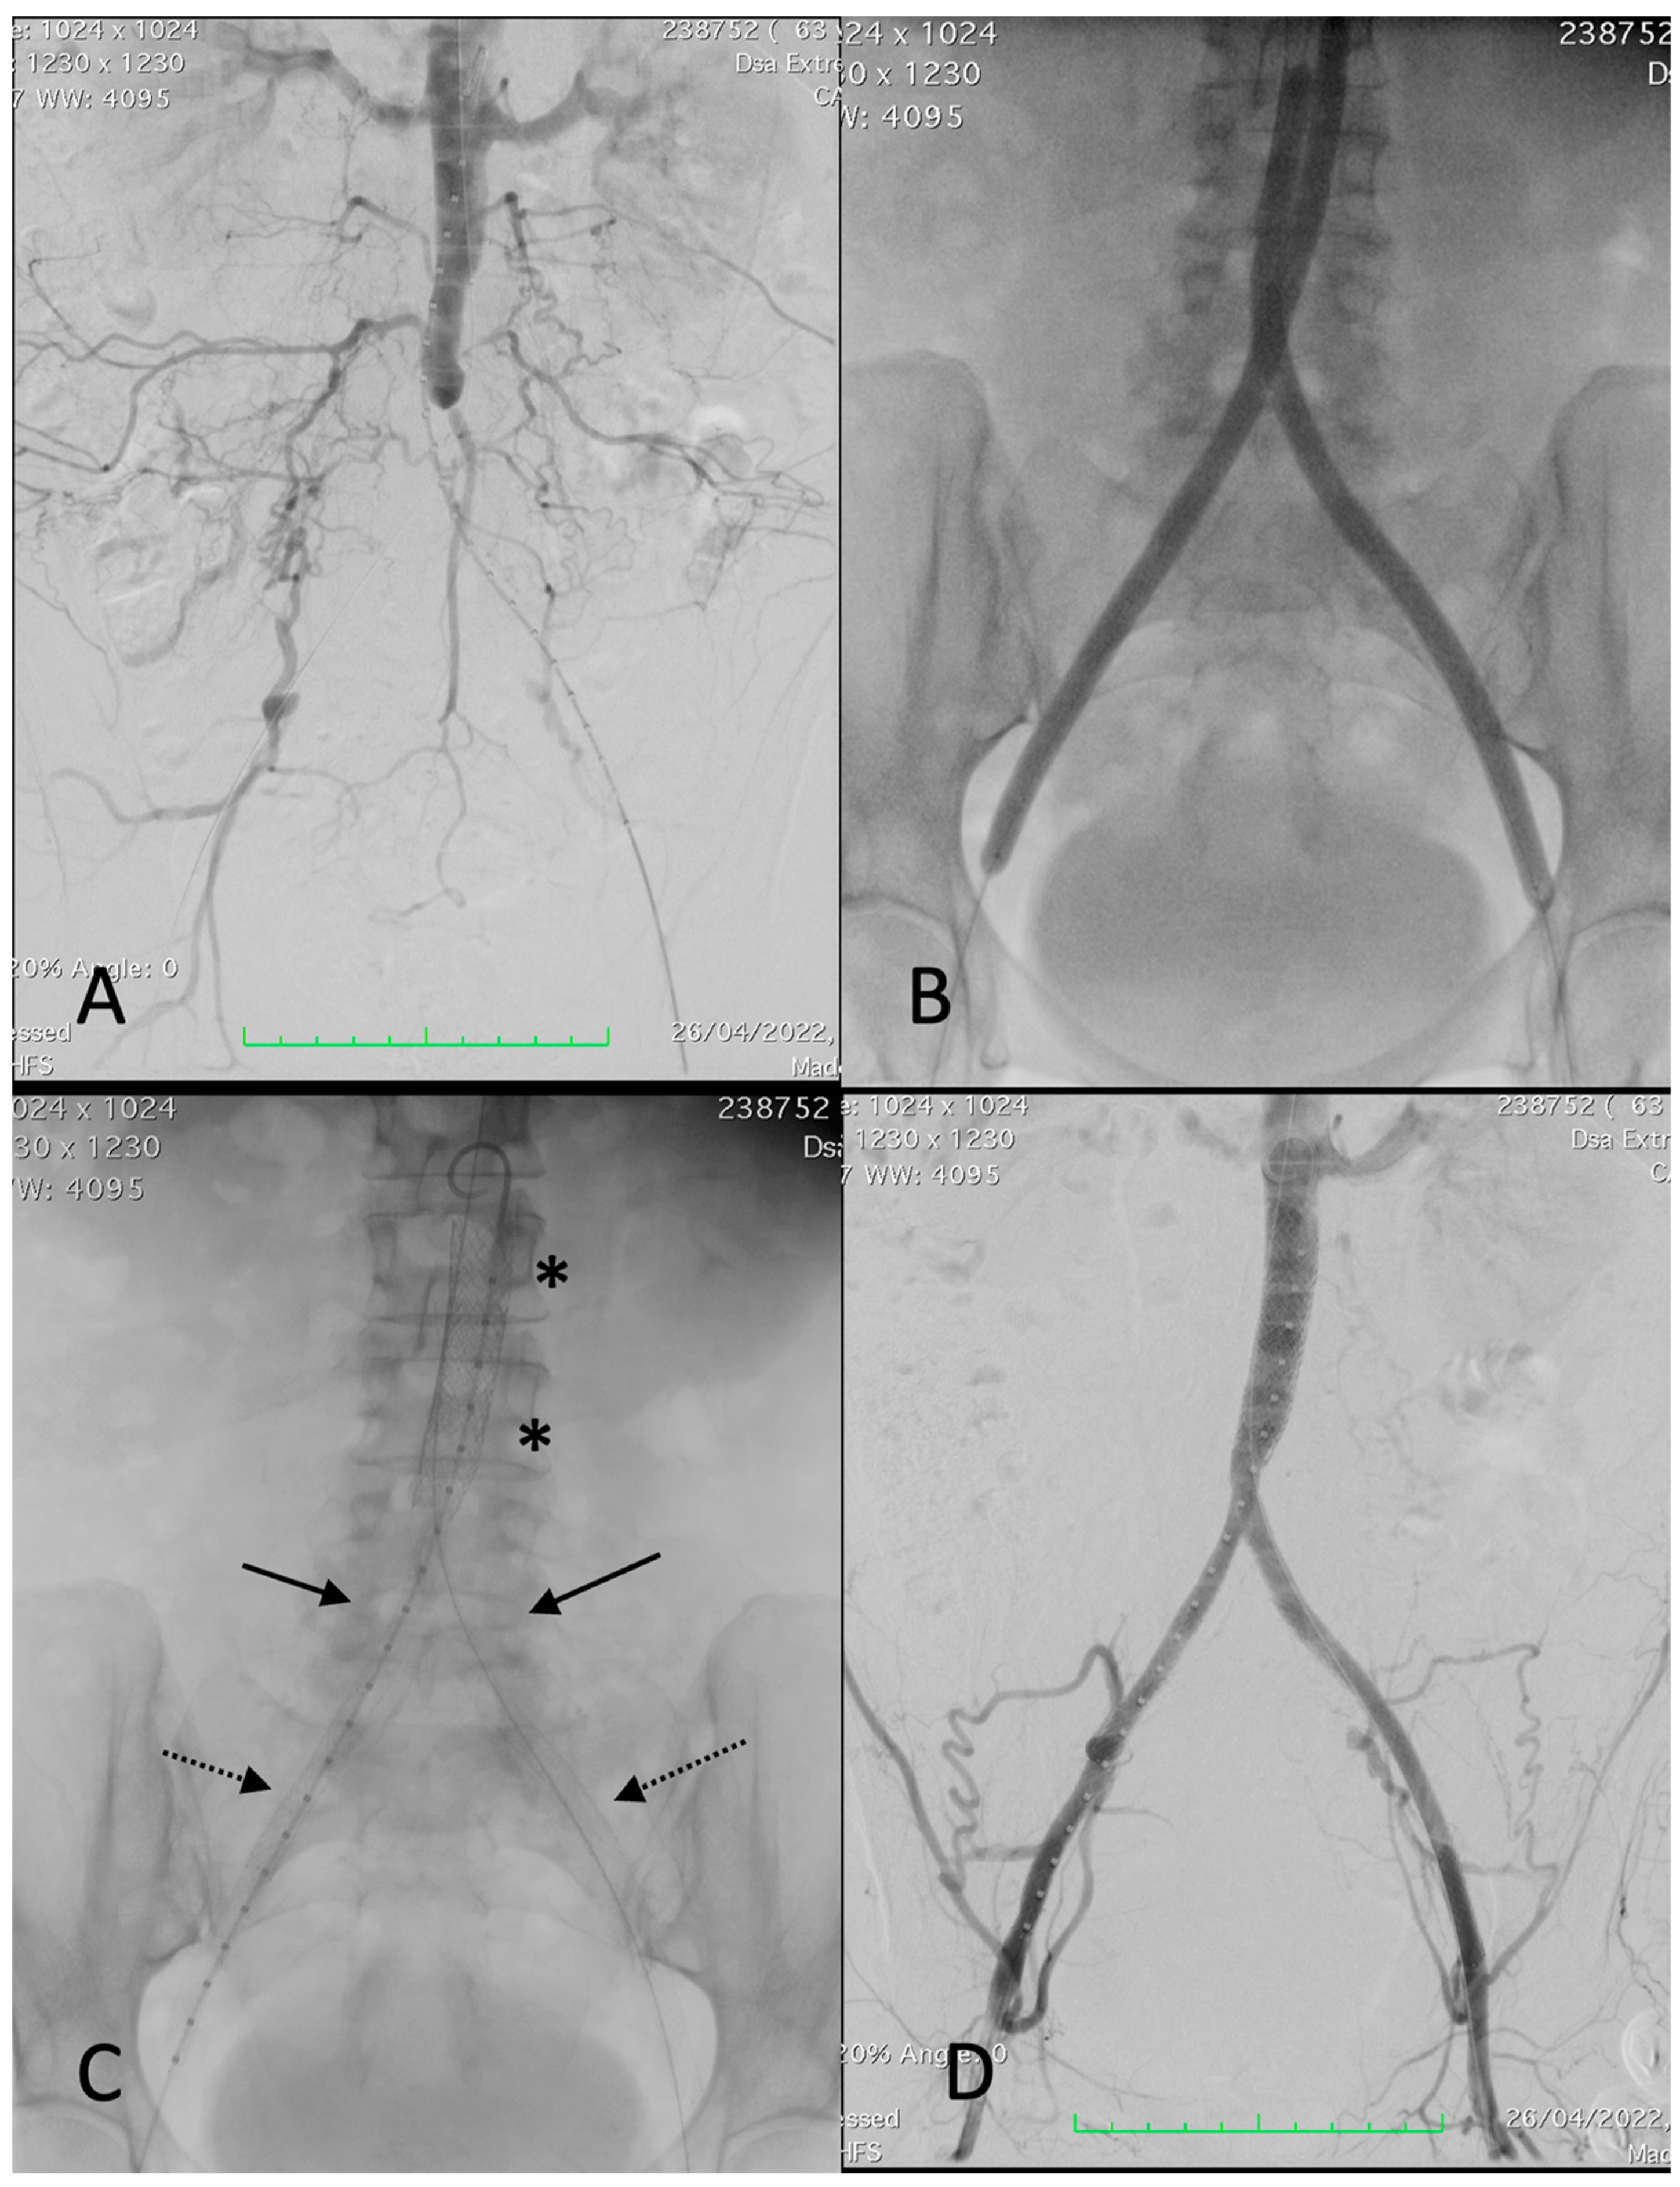

The CERAB technique has been described previously by Goverde et al. [1]. All patients had initial diagnostic angiography of the aorta and both iliac arteries with a standard contrast intra-arterial digital subtraction angiogram to outline the vascular anatomy and define the lesion characteristics (Figure 1). The endovascular procedures were performed by experienced vascular surgeons in a hybrid endovascular suite (Siemens Artis Zeego; Siemens, Munich, Germany). All patients were on aspirin pre-operatively. The procedures were performed under monitored anesthetic care. Percutaneous femoral accesses were used and 9 Fr or 11 Fr sheaths were introduced into one common femoral artery (BeGraft aortic covered stent recommended sheaths were 9 Fr for 12 mm stent diameter and 11 Fr for 14 mm diameter) and another 7 or 8 Fr sheath into the contralateral common femoral artery. Two closure devices (Perclose, Abbott Vascular, Abbott Park, IL, USA) were prepared during the femoral access for the 9 Fr sheaths. Periprocedural anticoagulation with weight-adjusted doses of intravenous heparin was administered. Stenosis and occlusions were passed, either subintimal or endoluminal, using 0.035′′ or 0.018′′ guidewires with the help of diagnostic catheters. After gaining re-entry into the lumen of the aorta, angiography confirmed the proper positioning for those with a subintimal passage. A 12 or 14 mm BeGraft aortic balloon-expandable covered stent (Bentley InnoMed, Hechingen, Germany) was implanted in the distal aorta, approximately 20 mm above the bifurcation. The proximal 2/3 part of the aortic stent was flared with a larger balloon (diameter was selected based on the proximal aortic lumen diameter without significant stenosis, considered the maximum post-dilatation diameter of 20 mm). Subsequently, two BeGraft Plus stent graft (Bentley InnoMed, Hechingen, Germany) balloon-expandable covered stents were deployed simultaneously, proximally in the distal 1/3 of the aortic stent and distally into the common iliac arteries. Their diameter varied from 7 to 8 mm depending on the distal common iliac artery lumen diameter, all without significant stenosis. When required, distal extensions were added, in those cases, Solaris self-expanding stent grafts (Scitech Medical, Goiania, Brasil). Nevertheless, in cases with a patent hypogastric artery and a fully diseased common and external iliac artery, a bare stent was deployed at that level. The sheaths were removed from the common femoral artery and the puncture sites were closed, usually using a closure device (Perclose Proglide, Abbott Vascular, IL, USA) or sutured in cases of open introduction. Technically, there are no anatomic or morphologic lesion boundaries for indication of the CERAB technique. When treating a total chronic occlusion, it was difficult to determine whether the guidewire was advanced intraluminally or subintimally; however, lesions were treated entirely with covered stents. Re-entry to the vascular lumen was always made as distal as possible in the patent aorta. When renal arteries or even visceral arteries were involved in the diseased segment, the use of protective balloons (3 cases) or chimney grafts (no cases) was considered. A concomitant endarterectomy of the femoral artery and/or external iliac artery was performed in cases of multilevel disease. Digital subtraction angiography (DSA) after each procedure recorded the stent implantation sites and runoff vessels to assess diameter improvement and potential complications, (such as dissection, thrombosis, or embolism). All DSA studies were conducted and interpreted by the same examiners (ESN, JAB). Post-intervention dual antiplatelet therapy with aspirin (100 mg/d) and clopidogrel (75 mg/d) was given for at least 4 weeks, with aspirin continued indefinitely thereafter. Statin therapy was also indicated.

Figure 1.

Procedural images of a 67-year-old female patient with left-sided Rutherford 4. (A) angiography showing thrombosis of common and external left iliac arteries and critical stenosis of the right common iliac artery with post-stenotic dilatation, extending into the distal aorta. (B) Deployment of a 12 × 39 mm BeGraft aortic (asterisks). (C) Deployment of two BeGraft Plus 7 × 57 mm stent grafts (arrow) and a Solaris stent graft (6 × 100 mm) at the left external iliac artery (dotted arrow). (D) Completion angiography showing a patent reconstruction with a good outflow.